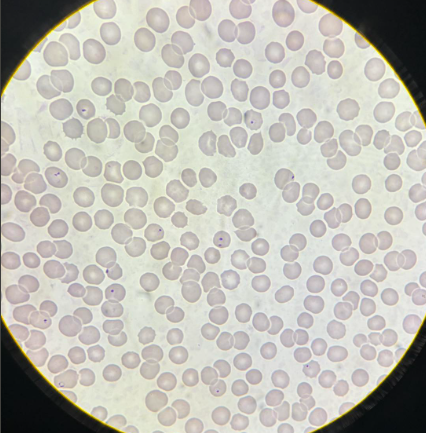

babesia sp stadia schizogonii krwinkowej

babesia sp stadia schizogonii krwinkowej